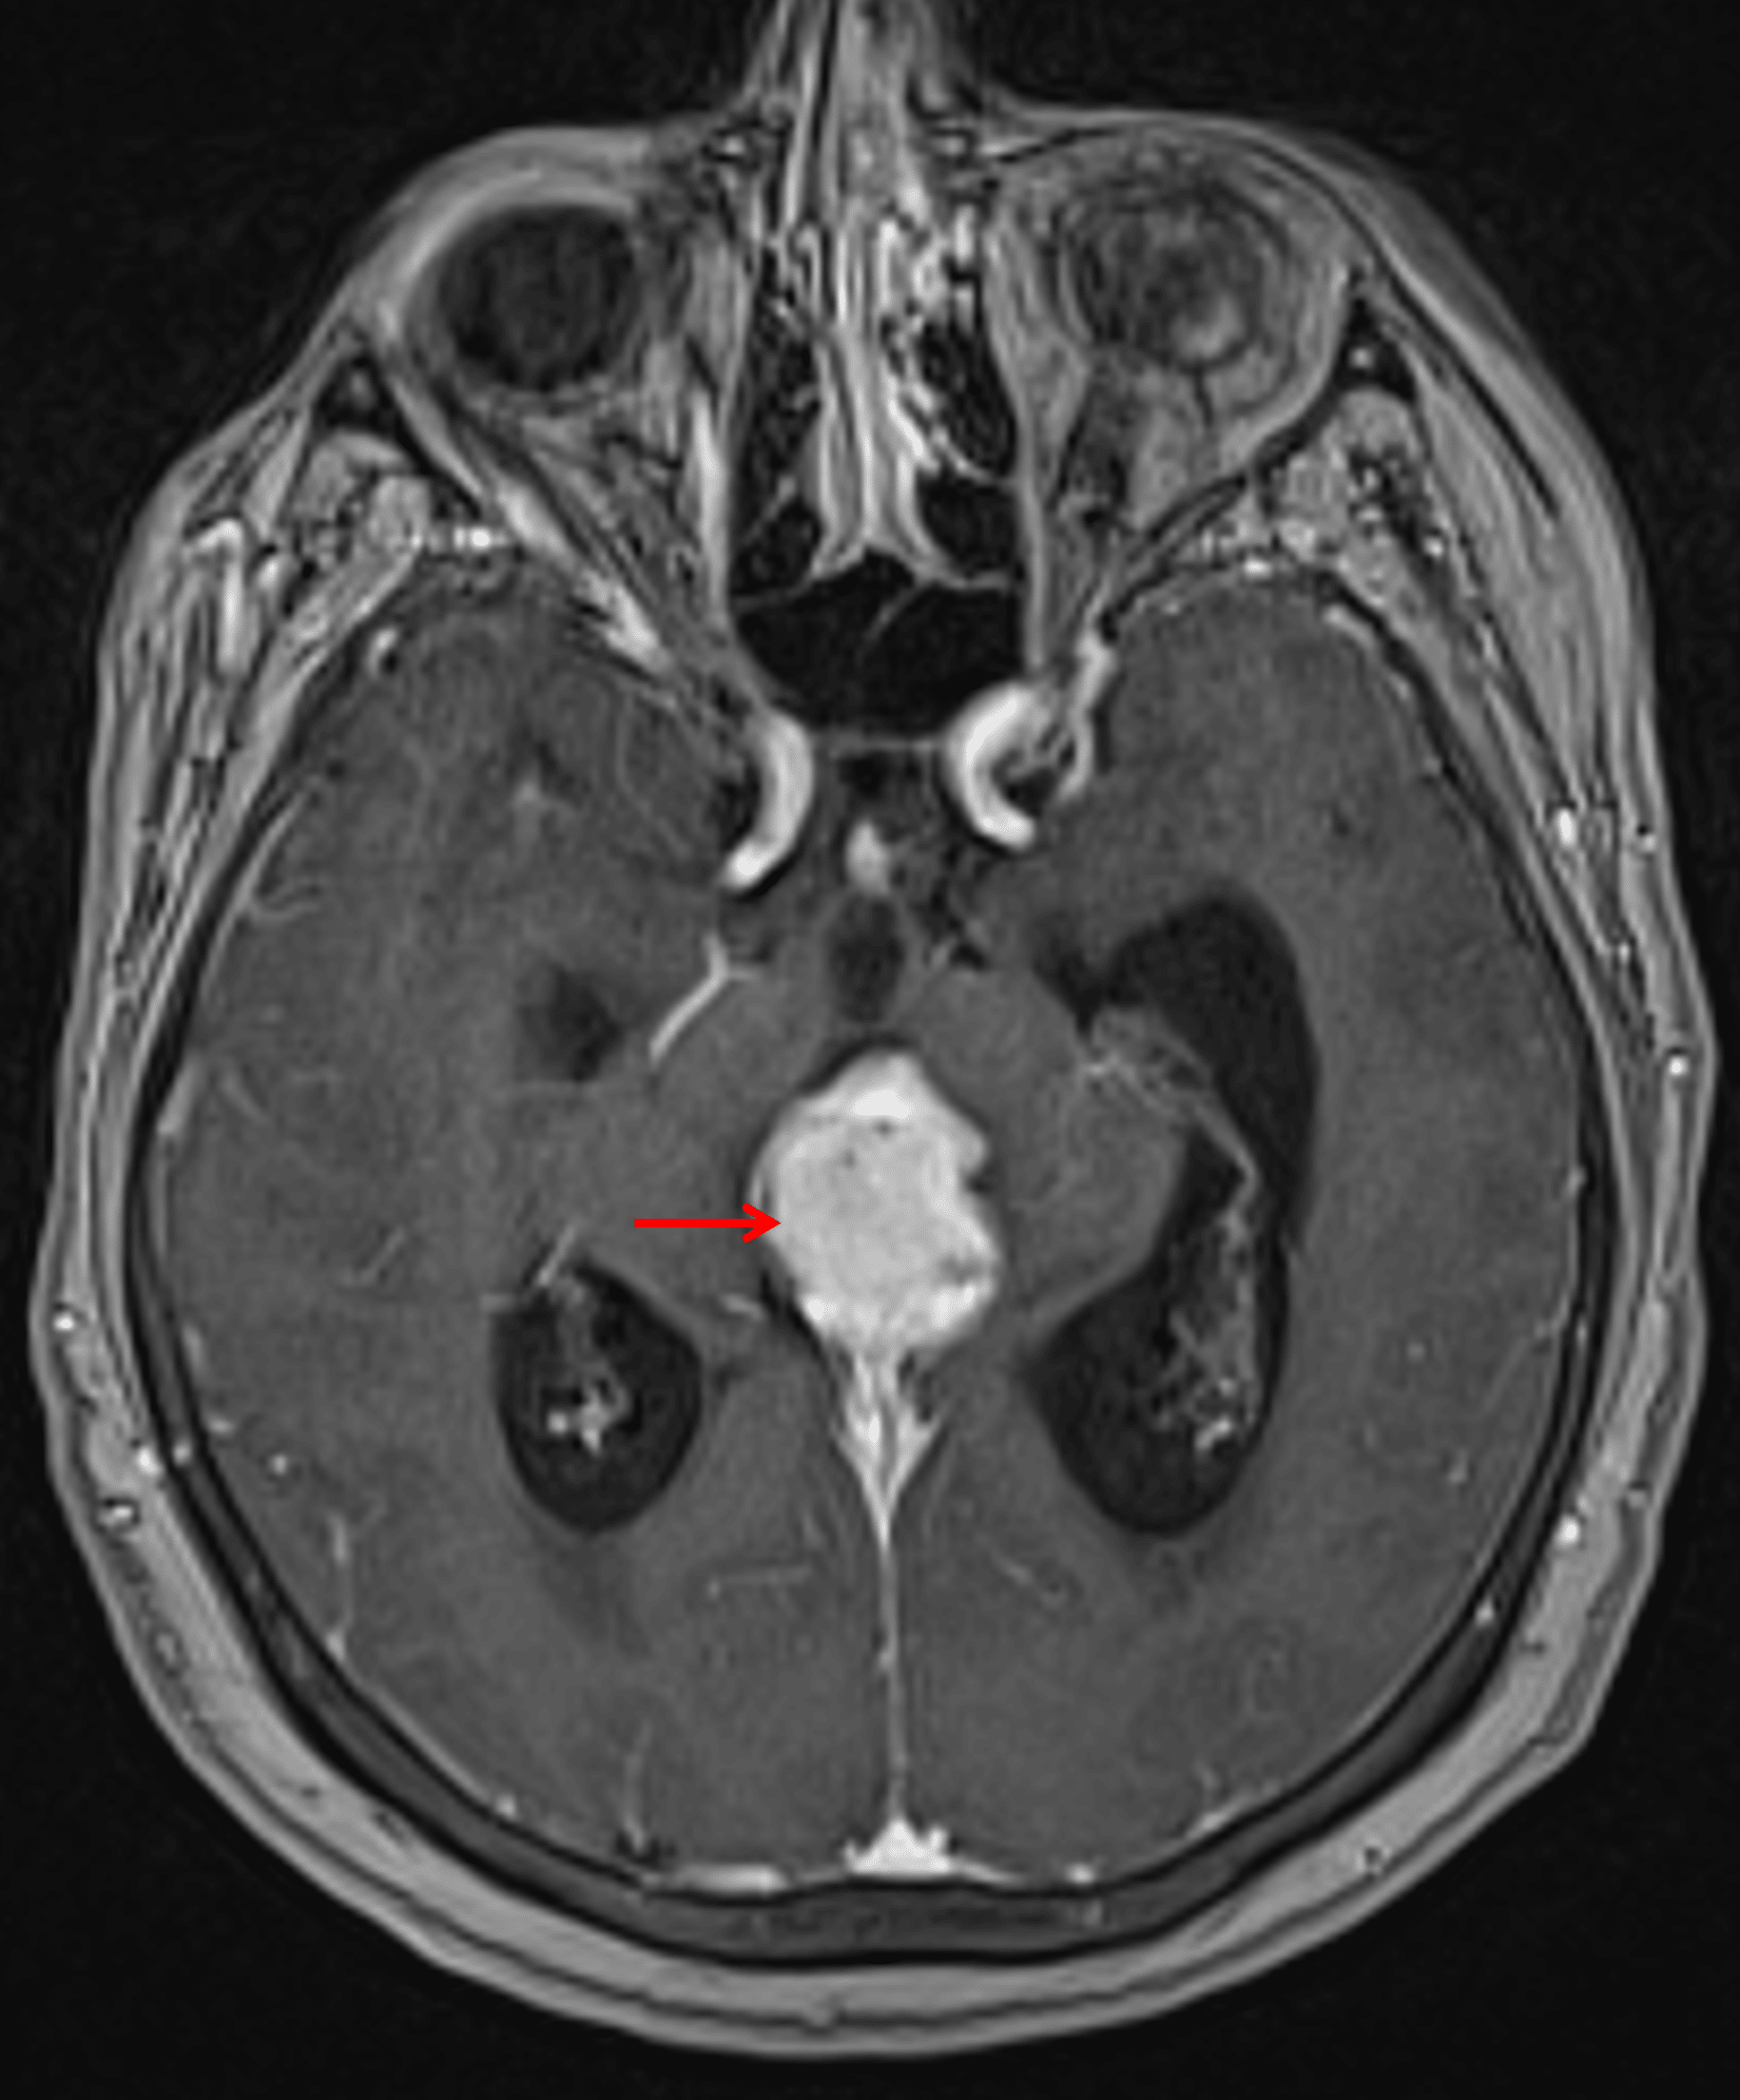

MRI

- Diffuse intermediate T2 signal, restricted diffusion, and avid enhancement

There is avid corresponding enhancement (red arrow).